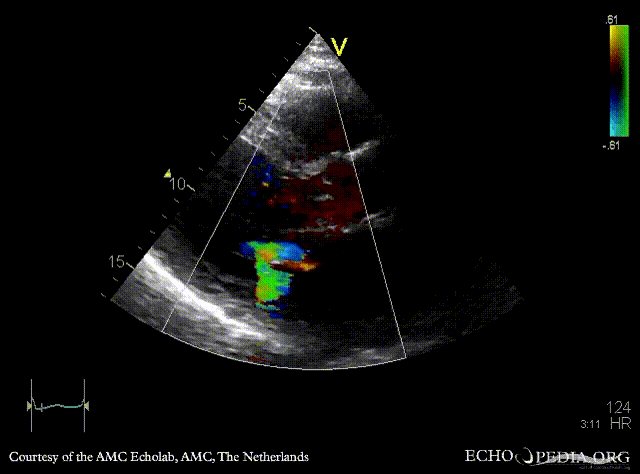

| A2CH | PLAX: Color Doppler, severe mitral regurgitation, excentric jet |

| A4CH: Color Doppler, severe mitral regurgitation, excentric jet | |